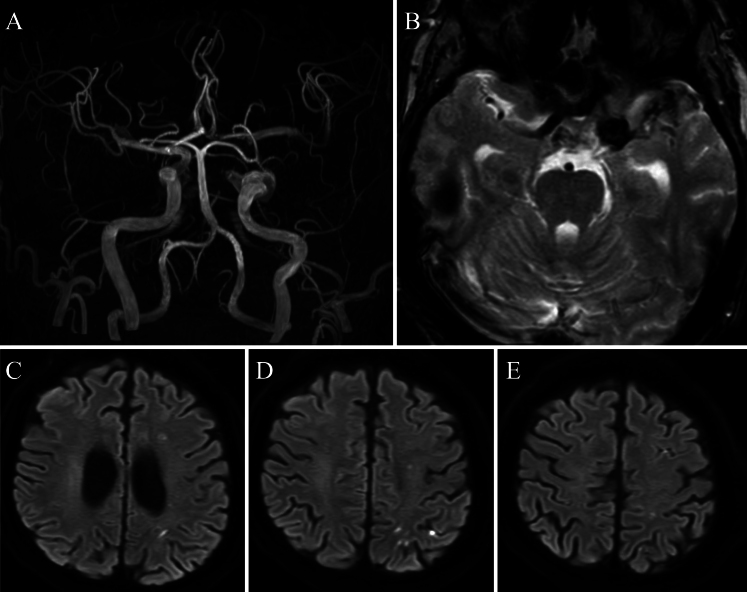

Observations: A 56-year-old man with poorly controlled diabetes experienced a sudden loss of vision in his left eye. Cranial imaging revealed invasive sphenoid sinusitis and CCF attributable to a ruptured infected CCA, as well as an unruptured infected supraclinoid internal carotid artery (ICA) aneurysm. After 3 weeks of medical treatment, the patient developed sudden impairment of higher function. MRI revealed occlusion of the distal ICA attributable to thrombosis of the supraclinoid ICA aneurysm. The anterior circulation was perfused from the contralateral side via the anterior communicating artery. Proximal occlusion with coils was performed, leading to ablation of the CCF.